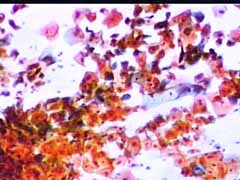

Papanicolaou: Πλακώδη επιθηλιακά κύτταρα κυρίως της επιφανειακήςστιβάδας, περίπου κατά50% και πλέον οξεόφιλα (16η ημέρα κύκλου!) . Ωστόσσο και αρκετά της διαμέσου και της παραβασικής, εν μέρει με διογκωμένους, ανισομεγέθειςαρραιοχρωματικούςδιαυγείςπυρήνεςKοιλοκυττάρωση.Η εικόνα συνηγορεί για δυσπλασία σοβαρού βαθμού.

Λόγω και του κολποσκοπικούευρήματος, μικροβιοψία που κατεδειξε ιστολογικώς CIN III

H γυναικα υπεβλήθη σε κωνοειδή εκτομή σε Νοσοκομείο... Επρόκειτο ιστολογικώς για CIN III που αφαιρεθηκε εντός του υγιούς..